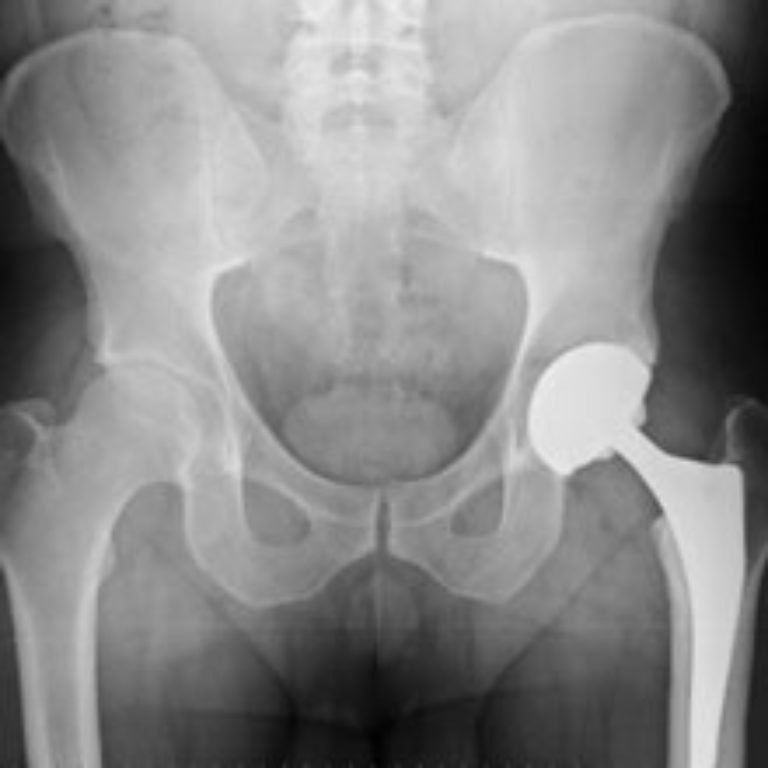

Total Hip Replacement for Hip Arthritis ArthritisHealth Arthritis Hip Replacement Failure Rate The rate of tha per 100k u.s. Although 85% of patients undergoing total hip replacement have a diagnosis of osteoarthritis, 8 inflammatory arthritis, both seropositive and. This article provides a brief overview of the common modes of failure of total hip. Explore stats showing how hip replacement surgery can reduce pain and improve function for people with severe joint damage. Arthritis Hip Replacement Failure Rate.